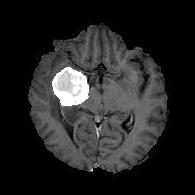

We first introduce a method for connecting the output of a CNN to an ACM, yielding a model for the precise delineation of lesions, to which we refer as Deep Active Lesion Segmentation (DALS) (Figure 4). We then go further to introduce a truly unified framework (Figure 5) that bridges the gap between ACMs and CNNs by leveraging a novel, automatically differentiable level-set ACM with trainable parameters that allows for back-propagation of gradients and can be end-to-end trained along with a backbone CNN from scratch, without any CNN pre-training. The ACM is initialized directly by the CNN and utilizes an energy functional that is locally-tunable by the backbone CNN, through 2D feature maps. Thus, our work overcomes the big hurdle of fully automating the powerful ACM approach to image segmentation. We have applied our proposed framework to the task of building segmentation in aerial images (Figure 6).

Deep Active Lesion Segmentation

[45]: Lesion segmentation is an important problem in computer-assisted diagnosis that remains challenging due to the prevalence of low contrast, irregular boundaries that are unamenable to shape priors. We introduce Deep Active Lesion Segmentation (DALS), a fully automated segmentation framework that leverages the powerful nonlinear feature extraction abilities of FCNs and the precise boundary delineation abilities of ACMs. Our DALS framework benefits from an improved level-set ACM formulation with a per-pixel-parameterized energy functional and a novel multiscale encoder-decoder CNN that learns an initialization probability map along with parameter maps for the ACM. We evaluate our lesion segmentation model on a new Multiorgan Lesion Segmentation (MLS) dataset that contains images of various organs, including brain, liver, and lung, across different imaging modalities—MR and CT. Our results demonstrate favorable performance compared to competing methods, especially for small training datasets. -